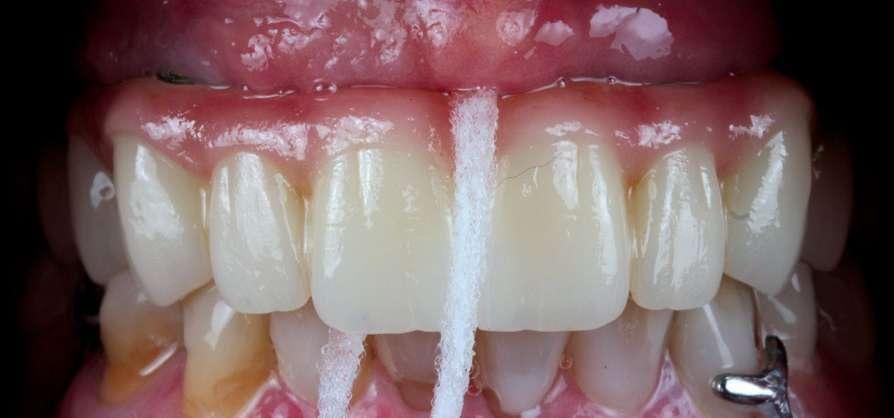

En su motivo de consulta demanda una “solución fija y menos voluminosa“ para rehabilitar su boca. (Fig. 1 y 2).

Todos estos parámetros fueron corregidos en el diseño de sonrisa inicial y encerado digital. (Figura 3, 4 y 5).